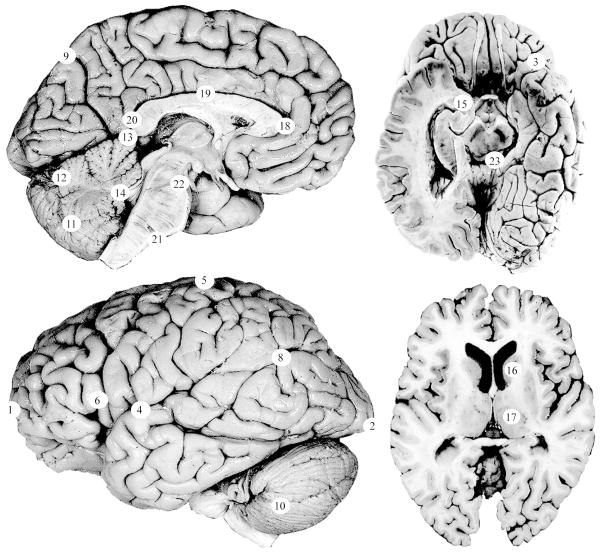

Statistical Shape Analysis

Twenty-three (23) landmarks representing cortical and subcortical structures on the midline and left side of the brain were used to assess brain shape (Table 2, Figures 1–2). Landmarks were collected blind to sex and cleft status using eTDIPS, a multidimensional volume visualization analysis software that allows landmarks to be placed on any of the three planar views or directly on a 3D reconstruction of the brain25–26. Landmarks were only collected on the left side of the brain because when Weinberg et al. (2009)16 analyzed brain shape in adults with CL/P, they used unilateral left brain landmarks. For comparative purposes, it was beneficial to employ the same technique. All of the landmarks that were used in this project were validated in an inter- and intra-observer error study. The average intraobserver error was 1.9 mm with a range of 0.72 to 5.6 mm and the average interobserver error was 1.1 mm with a range of 0.40 mm to 3.4 mm.

Figure 1. Landmarks used to assess brain shape.

Twenty-three landmarks were used to assess brain shape. The landmark numbers correspond to the numbered list in Table 1. Detailed landmark protocols and additional images of these landmarks are available at http://www.hopkinsmedicine.org/fae/vbd.htm. Photographs were adapted with permission from the Digital Anatomist Project24.

Twenty-three cortical and subcortical landmarks were used to characterize brain shape. The numbers in the left column correspond with the numbered landmarks in the figures.